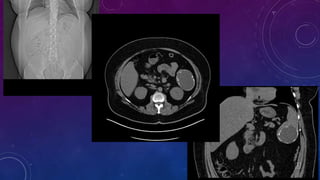

THEME : ABDOMINAL CALCIFICATIONS

MULTIPLE GALL STONES

GB AND RIGHT RENAL CALCULI.

CHRONIC CALCIFIC PANCREATITIS

CT SCOUT RADIOGRAPHS